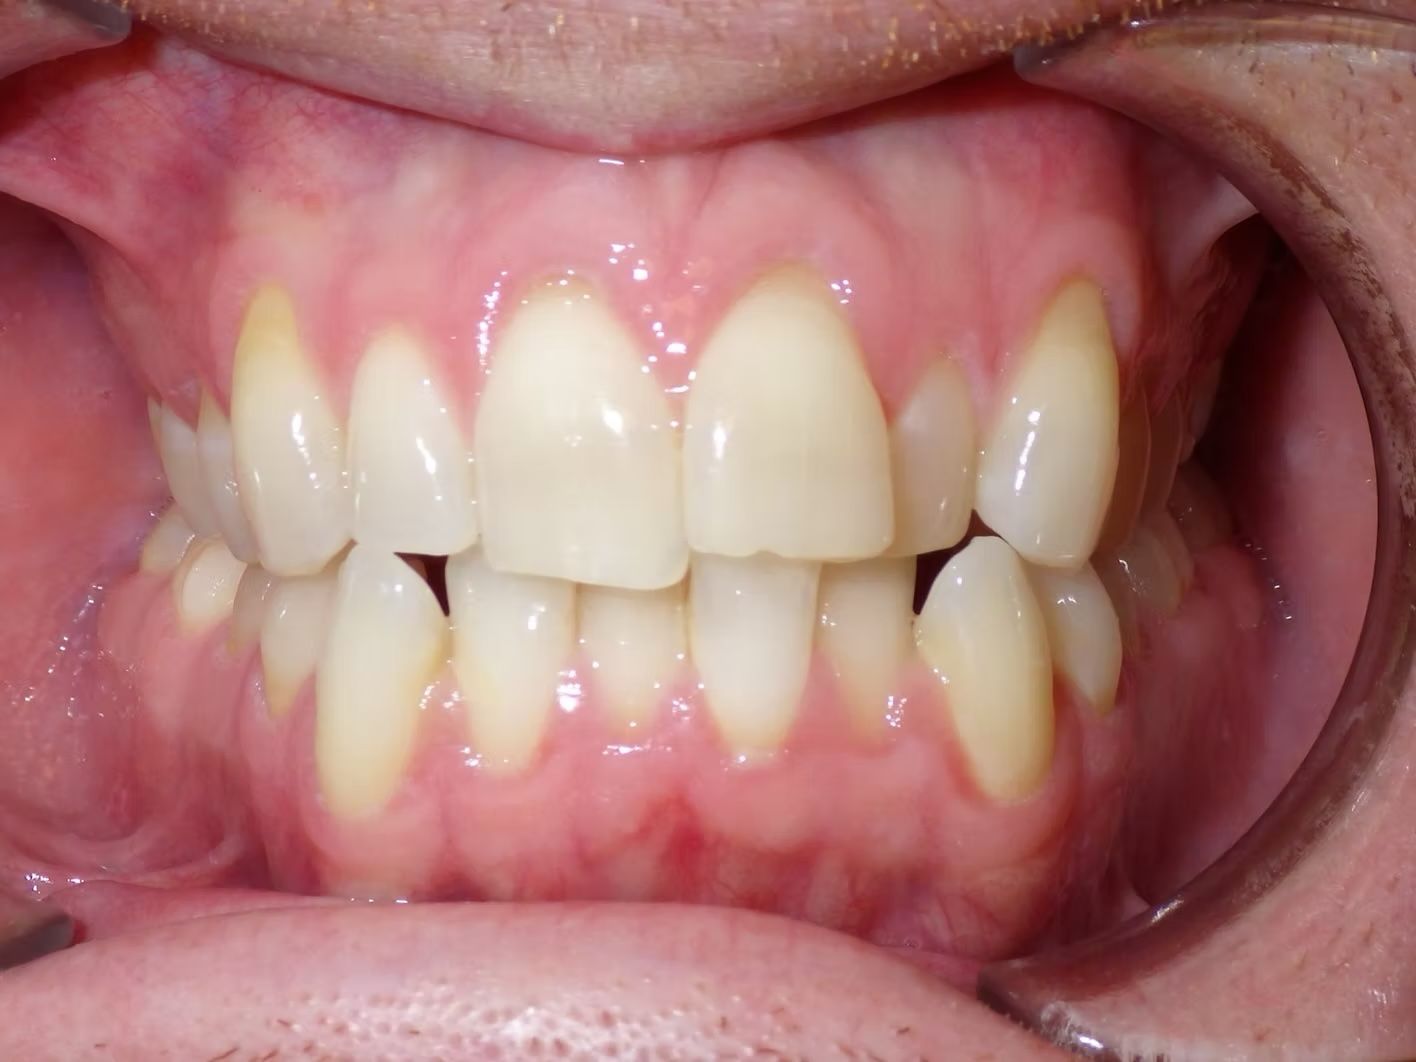

Emily

Emily didn't like how her top teeth were turned in and the lower teeth were crowded. Her bite was slightly off on both sides. Emily just needed upper and lower braces to correct her dental alignment and some rubber bands to correct the bite. She absolutely loves her teeth now!